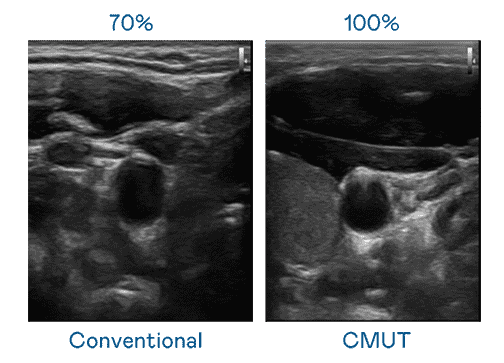

CMUT 技术是一种用电容式微机电元件来产生超音波讯号的技术。。。与传统 PZT 压电式技术相比,,,CMUT 频宽增加 30%,,,更宽频的超音波讯号让影像解析度大幅提升,,是实现高影像品质医疗超音波扫描、、、、促进精准医疗发展的关键技术。。。

大频宽带来超清晰影像

超音波影像的解析度高低,,首先取决于探头能发出的讯号频宽。。冰球突破 CMUT 可提供高清晰的超音波讯号,,,提供高频宽、、、、高灵敏度、、、影像纹理细节更高的超音波影像,,协助医护人员缩短影像判读时间及利用精准的医疗影像进行诊断。。。。